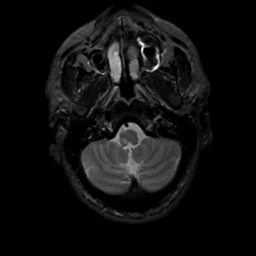

MR Study #3, February 24, 1991 -- Slice #6

[Home][Help][Clinical][Tour 1][Tour 2] Slice 6